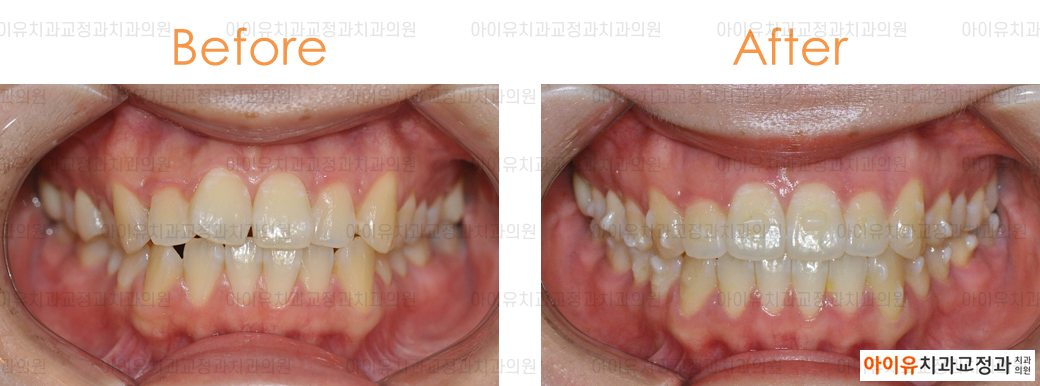

아래는 지난 몇 년간 울산 아이유치과에서 진행한 인비절라인 치료결과, 전후사진 중 일부입니다.

만 24세 / 앞니 비뚤함 / 치료기간 1.5년 / 인비절라인 사용

위의 치료 결과에서 알 수 있듯 대부분의 경우에서 투명교정은 기존의 브라켓 교정과 동일한 효과를 얻을 수 있습니다.